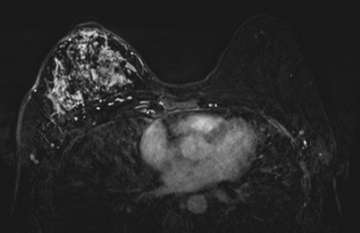

MRI

The most common imaging features of IBC are diffuse skin thickening and edema. Extensive or segmental non mass-like enhancements are commonly seen (Figure 2). MRI can accurately detect a primary breast lesion in 98-100% of cases, which is superior to mammography or ultrasound. Diffusion-restricting irregular and spiculated mass or masses can be seen with rapid enhancement and delayed or plateau washout characteristics. Thickened skin may also exhibit diffusion restriction and focal enhancement. Tumor emboli in the lymphatic spaces may manifest as reticular/dendritic enhancement. MRI is the best imaging modality to accurately predict local treatment response based on the size of the tumor per Response Evaluation Criteria in Solid Tumors 1.1 criteria. MRI is also useful in assessing the extent of extraparenchymal involvement, including local chest wall invasion as well as lymphadenopathy.